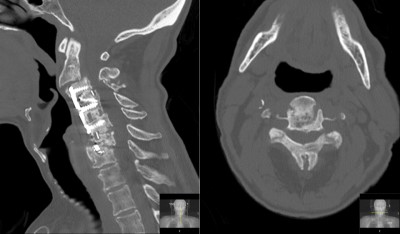

CT c-spine (sagittal left, axial right) obtained in ER showing malalignment and stenosis.